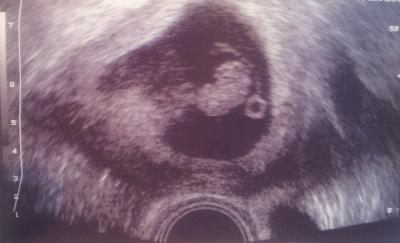

Hallo ihr Lieben, möchte noch kurz von meinem FA-Termin berichten. Dieser ist zwar schon zwei Tage her, aber ich habe gerade einiges an der Arbeit und auch zu Hause zu tun, so dass ich nicht eher dazu kam. Es ist alles in bester Ordnung und das Kleine war für seine SSW genau richtig entwickelt. Da ich Samstag in meine kritische Woche (FG im März) komme, darf ich in einer Woche schon wieder zum FA, weil er in zwei Wochen Urlaub hat. Aber ich bin dieses Mal echt ganz guter Dinge und hoffe, das rächt sich nicht noch. Anbei noch mein US-Bildchen. :-) Glg Ella

Bild zu Mein FA-Termin (etwas verspätet) - Forum für Mai - Mamis